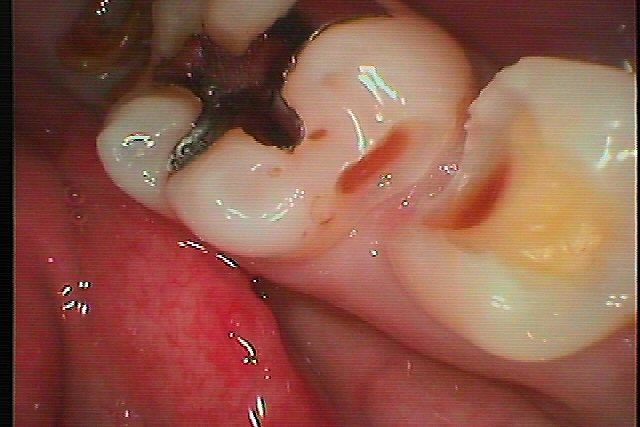

左下5,6間の虫歯治療|お知らせ |広島市安佐南区の歯科医院 左下5,6間の虫歯治療 トップ お知らせ・ブログ お知らせ 左下5,6間の虫歯治療 左下5,6間の虫歯治療 歯の間に虫歯があります 隣も虫歯でした 悪い所を取っていきました CRにて除去する部分と覆罩して 型どりを行っていきました セラミックにて修復しています。 Web診療予約 初めての方へ 選ばれ続ける理由 院内設備について 歯が痛いしみる一般歯科 歯がぐらぐらする歯周病 健康な歯を保ちたい予防歯科 子供の虫歯予防をしたい小児歯科 銀歯をセラミックに審美歯科 白い歯を目指しませんか?ホワイトニング 矯正専門医がいるので安心矯正歯科 抜けた歯を補いたいインプラント・入れ歯 医院案内 スタッフ紹介 メリィハウス歯科クリニックオフィシャルホームページ ラベンダー歯科クリニックオフィシャルホームページ お知らせ・ブログ ホーム 診療科目 一般歯科 歯周病治療 予防治療 小児歯科 審美治療 ホワイトニング 矯正歯科 入れ歯・インプラント マウスピース矯正 初めての方へ 院長・スタッフ 設備紹介 医院案内・アクセス メニューを閉じる